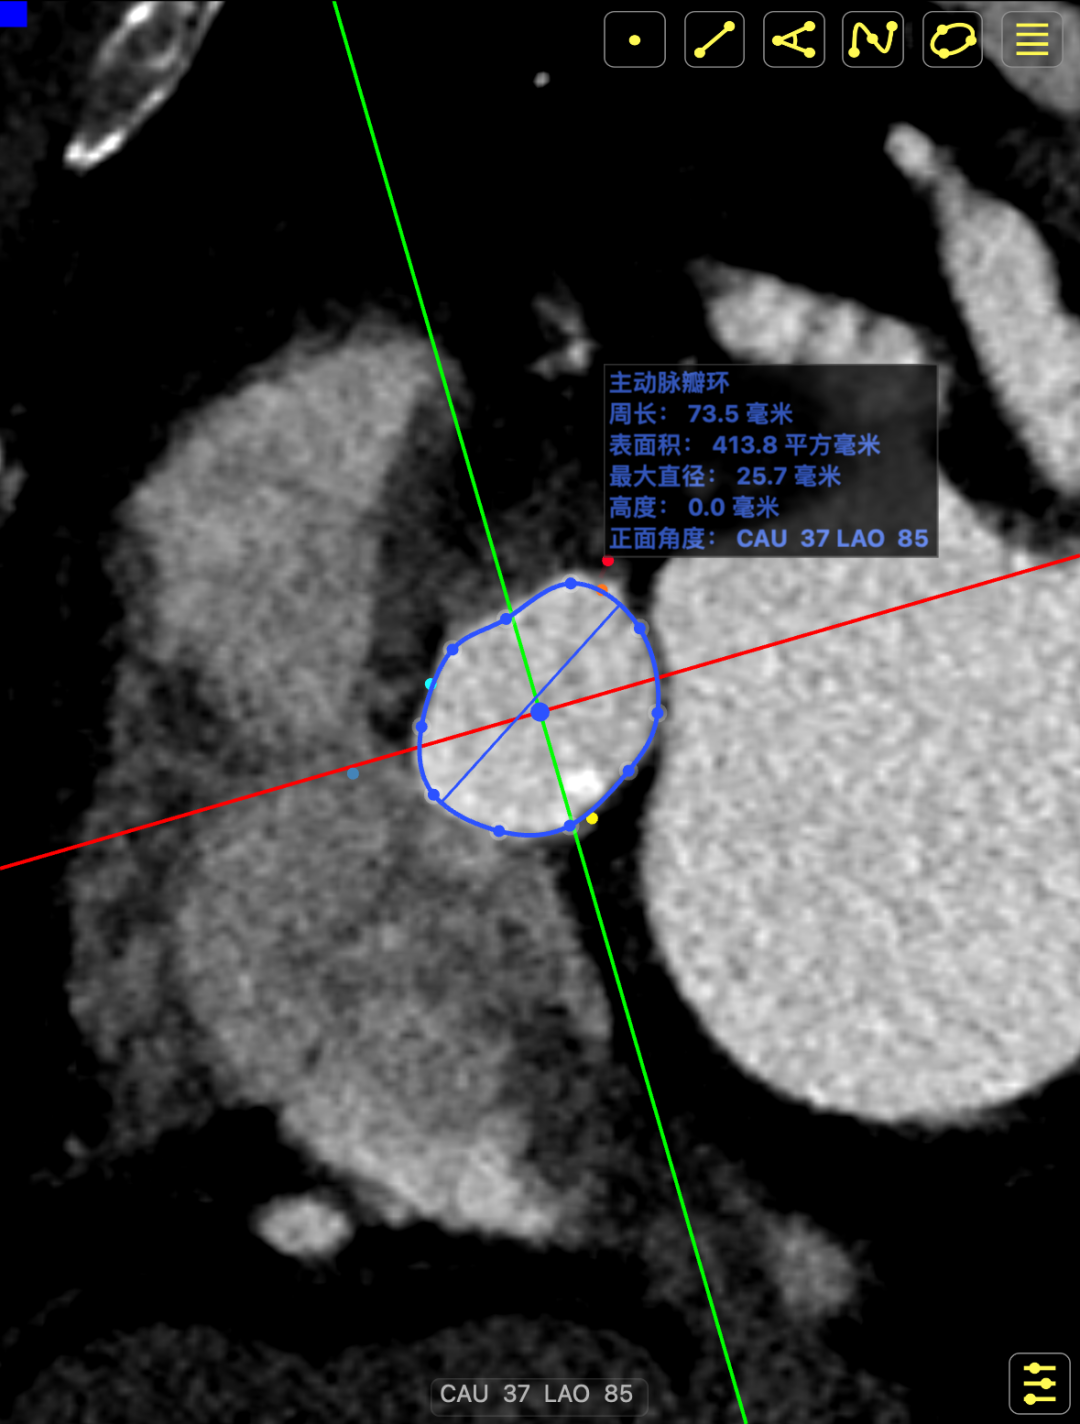

CT影像

CT影像